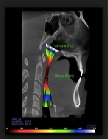

Understanding Nasal Breathing: The Key to Evaluating and Treating Sleep Disordered Breathing in Adults and Children

Peter Catalano, MD1*, John Walker, DMD2